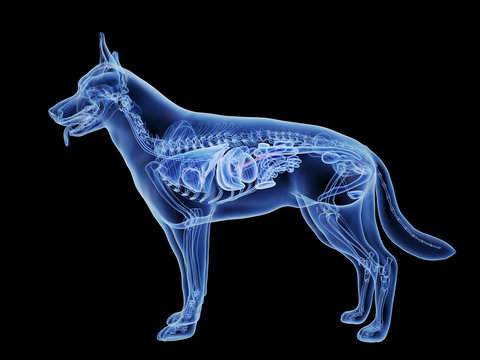

Dog paw x ray cheap

Dog paw x ray cheap, X RAY DOG S PAW VETERINARY MEDICINE Stock Photo Alamy cheap

Product Name: Dog paw x ray cheap